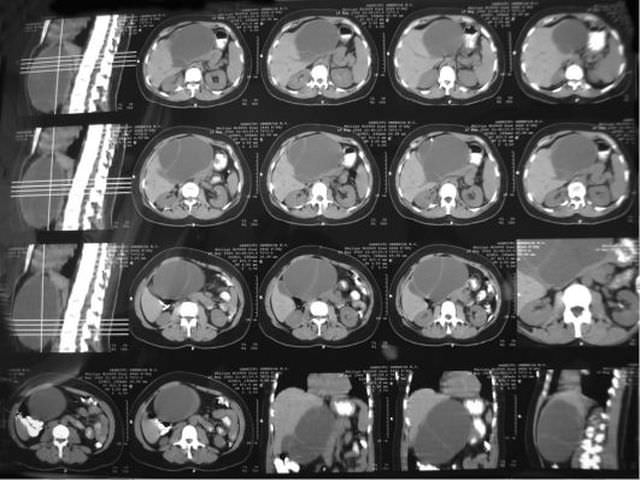

Кт показало 2

Кт показало 2 108 фото